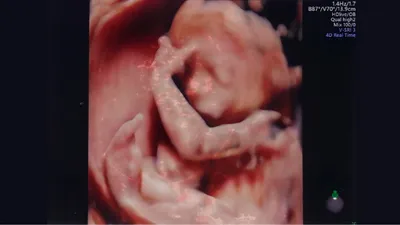

4Dエコーは、3Dエコーに時間の要素を追加したもので、動画で赤ちゃんの様子をとらえられるのが特徴です。おなかの中であくびをしたり、手足を動かしたりする様子もはっきりわかります。

見られるもの: 胎児の動き、表情、あくび、指しゃぶり、まばたきなどの動作。顔立ちや性別の確認も可能ですが、性別の確定は必ずしも正確ではありません。

赤ちゃんを立体的にとらえるため、顔立ちもはっきりわかります。

4Dエコーは動画なので、運が良ければおなかの中で赤ちゃんがどのように過ごしているかが見られます。